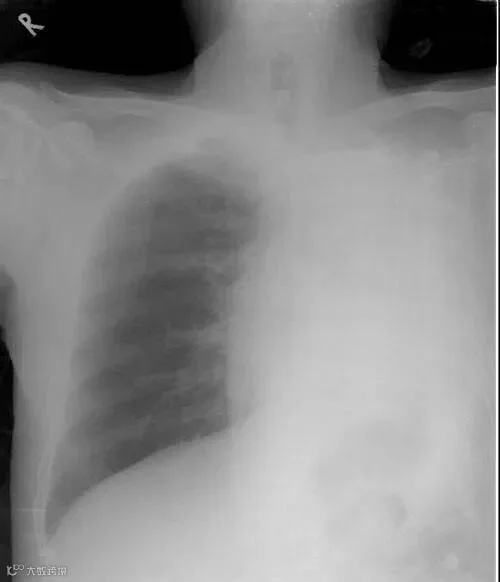

可为什么有些人一旦感染,就迅速发展为「白肺样」,甚至死亡?

“白肺”,一般是指的重症肺炎其在X光检查下的表现,肺部显影呈一大片的白色状而得名。其最常见的病因是感染,其次是弥漫性肺泡出血综合症、急性呼吸窘迫综合征(ARDS)等。

如果炎症此时刚好在肺部,那么人的肺部细胞就会受损,呼吸功能便会减弱。

如果白色面积太大,则表示炎症已经发展到了非常危险的阶段。

且前期免疫系统为了快速大量地杀死病毒,会聚集大量白细胞在此,白细胞的运输靠的是体液和血液。

液体大量在肺部聚集,唯一的结果就是阻塞肺部,使得人们无法呼吸。

所以很多时候,过分的免疫反应,是造成死亡的直接原因。